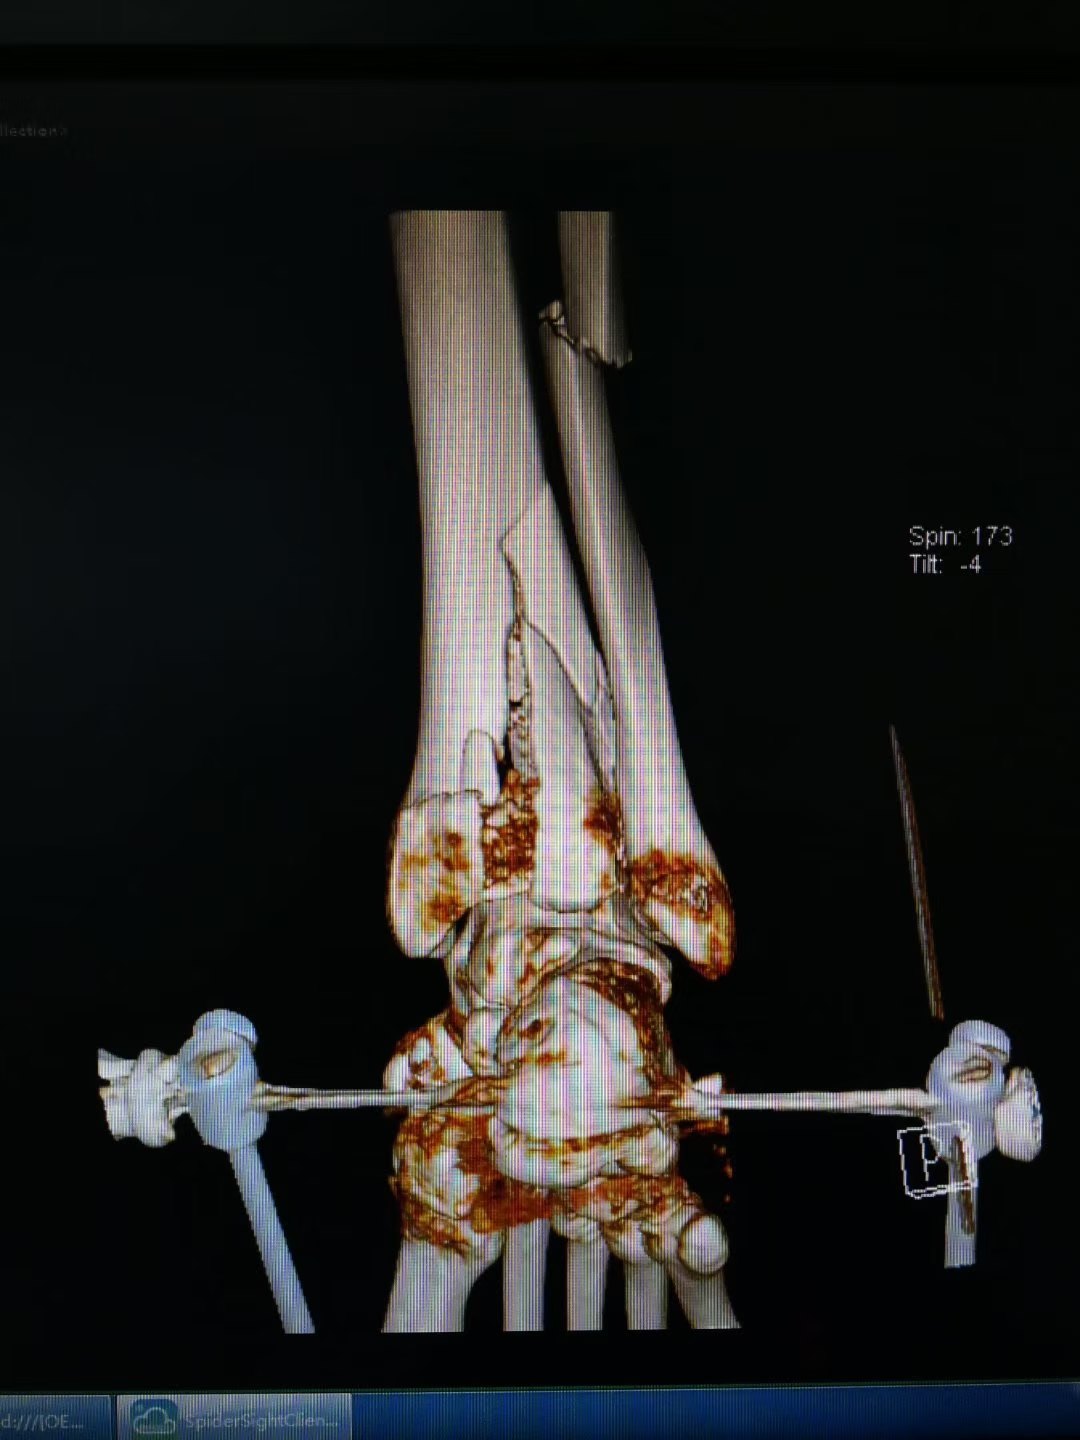

2个典型病例教会你踝部骨折外固定 医学界 助力医生临床决策和职业成长